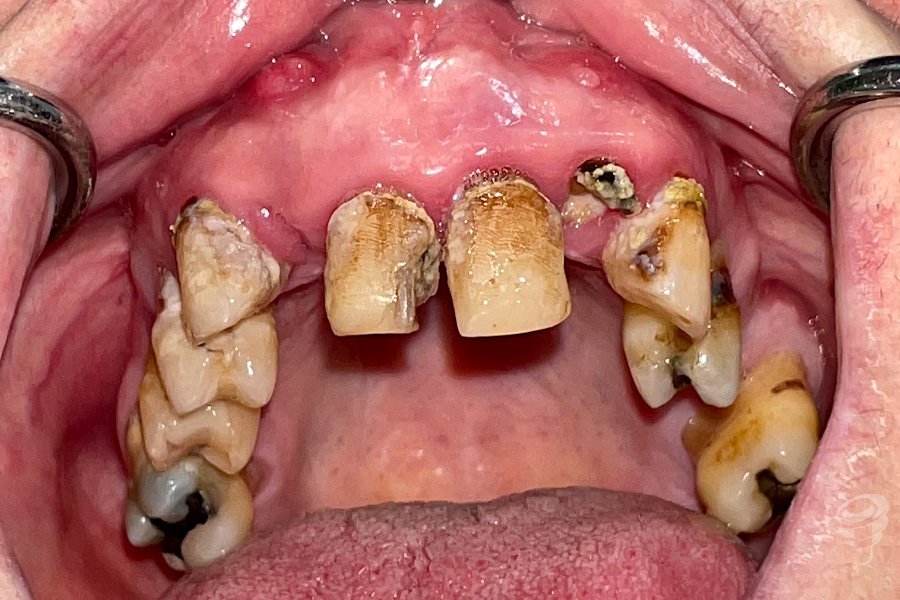

Orto postoperatorio inmediato + Carga inmediata. (Imagen 10 y 11)

Orto a los 3 años de evolución + Prótesis definitiva. (Imagen 12 y 13)